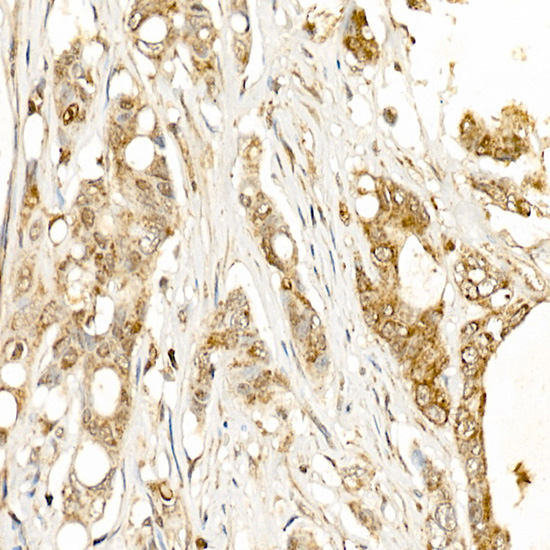

Immunohistochemistry of paraffin-embedded human colon carcinoma using KLK1 Rabbit pAb.